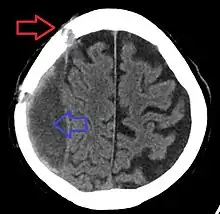

Subdural hematomas occur most often around the tops and sides of the frontal and parietal lobes.[3][2] They also occur in the posterior cranial fossa, and near the falx cerebri and tentorium cerebelli.[3] Unlike epidural hematomas, which cannot expand past the sutures of the skull, subdural hematomas can expand along the inside of the skull, creating a concave shape that follows the curve of the brain, stopping only at dural reflections like the tentorium cerebelli and falx cerebri.

On a CT scan, subdural hematomas are classically crescent-shaped, with a concave surface away from the skull. However, they can have a convex appearance, especially in the early stages of bleeding. This may cause difficulty in distinguishing between subdural and epidural hemorrhages. A more reliable indicator of subdural hemorrhage is its involvement of a larger portion of the cerebral hemisphere. Subdural blood can also be seen as a layering density along the tentorium cerebelli. This can be a chronic, stable process, since the feeding system is low-pressure. In such cases, subtle signs of bleeding—such as effacement of sulci or medial displacement of the junction between gray matter and white matter—may be apparent.

Fresh subdural bleeding is hyperdense, but becomes more hypodense over time due to dissolution of cellular elements. After 3–14 days, the bleeding becomes isodense with brain tissue and may therefore be missed.[20] Subsequently, it will become more hypodense than brain tissue.[21]